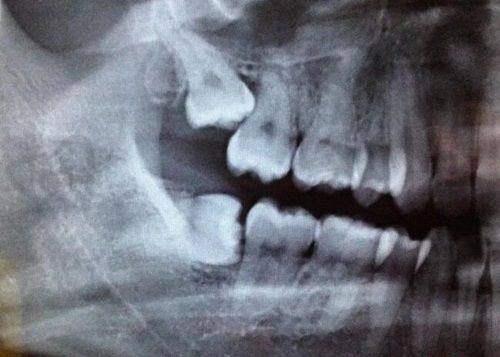

曲靖舒尔口腔特别注重口腔诊疗设备和技术的引进。院内引进了国内外精良的口腔诊疗设备,如口腔CT、美国iTero正畸口扫、丹麦3Shape口扫等。在技术方面,有精良的数字化种植技术和数字化正畸技术。这些精良设备和技术的应用,可以有效提升口腔诊疗的效率,让口腔诊疗更加便捷,还能提升口腔检查的精细程度,同时也能有效缩短就诊时间,减少患者的痛苦。